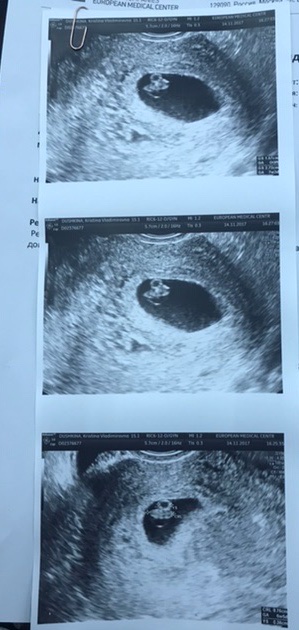

Нашла своё старое узи с сыном на этом сроке

я не очень понимаю как там смотреть))Но вот мои трое)Внизу два парня,сверху девчонка)